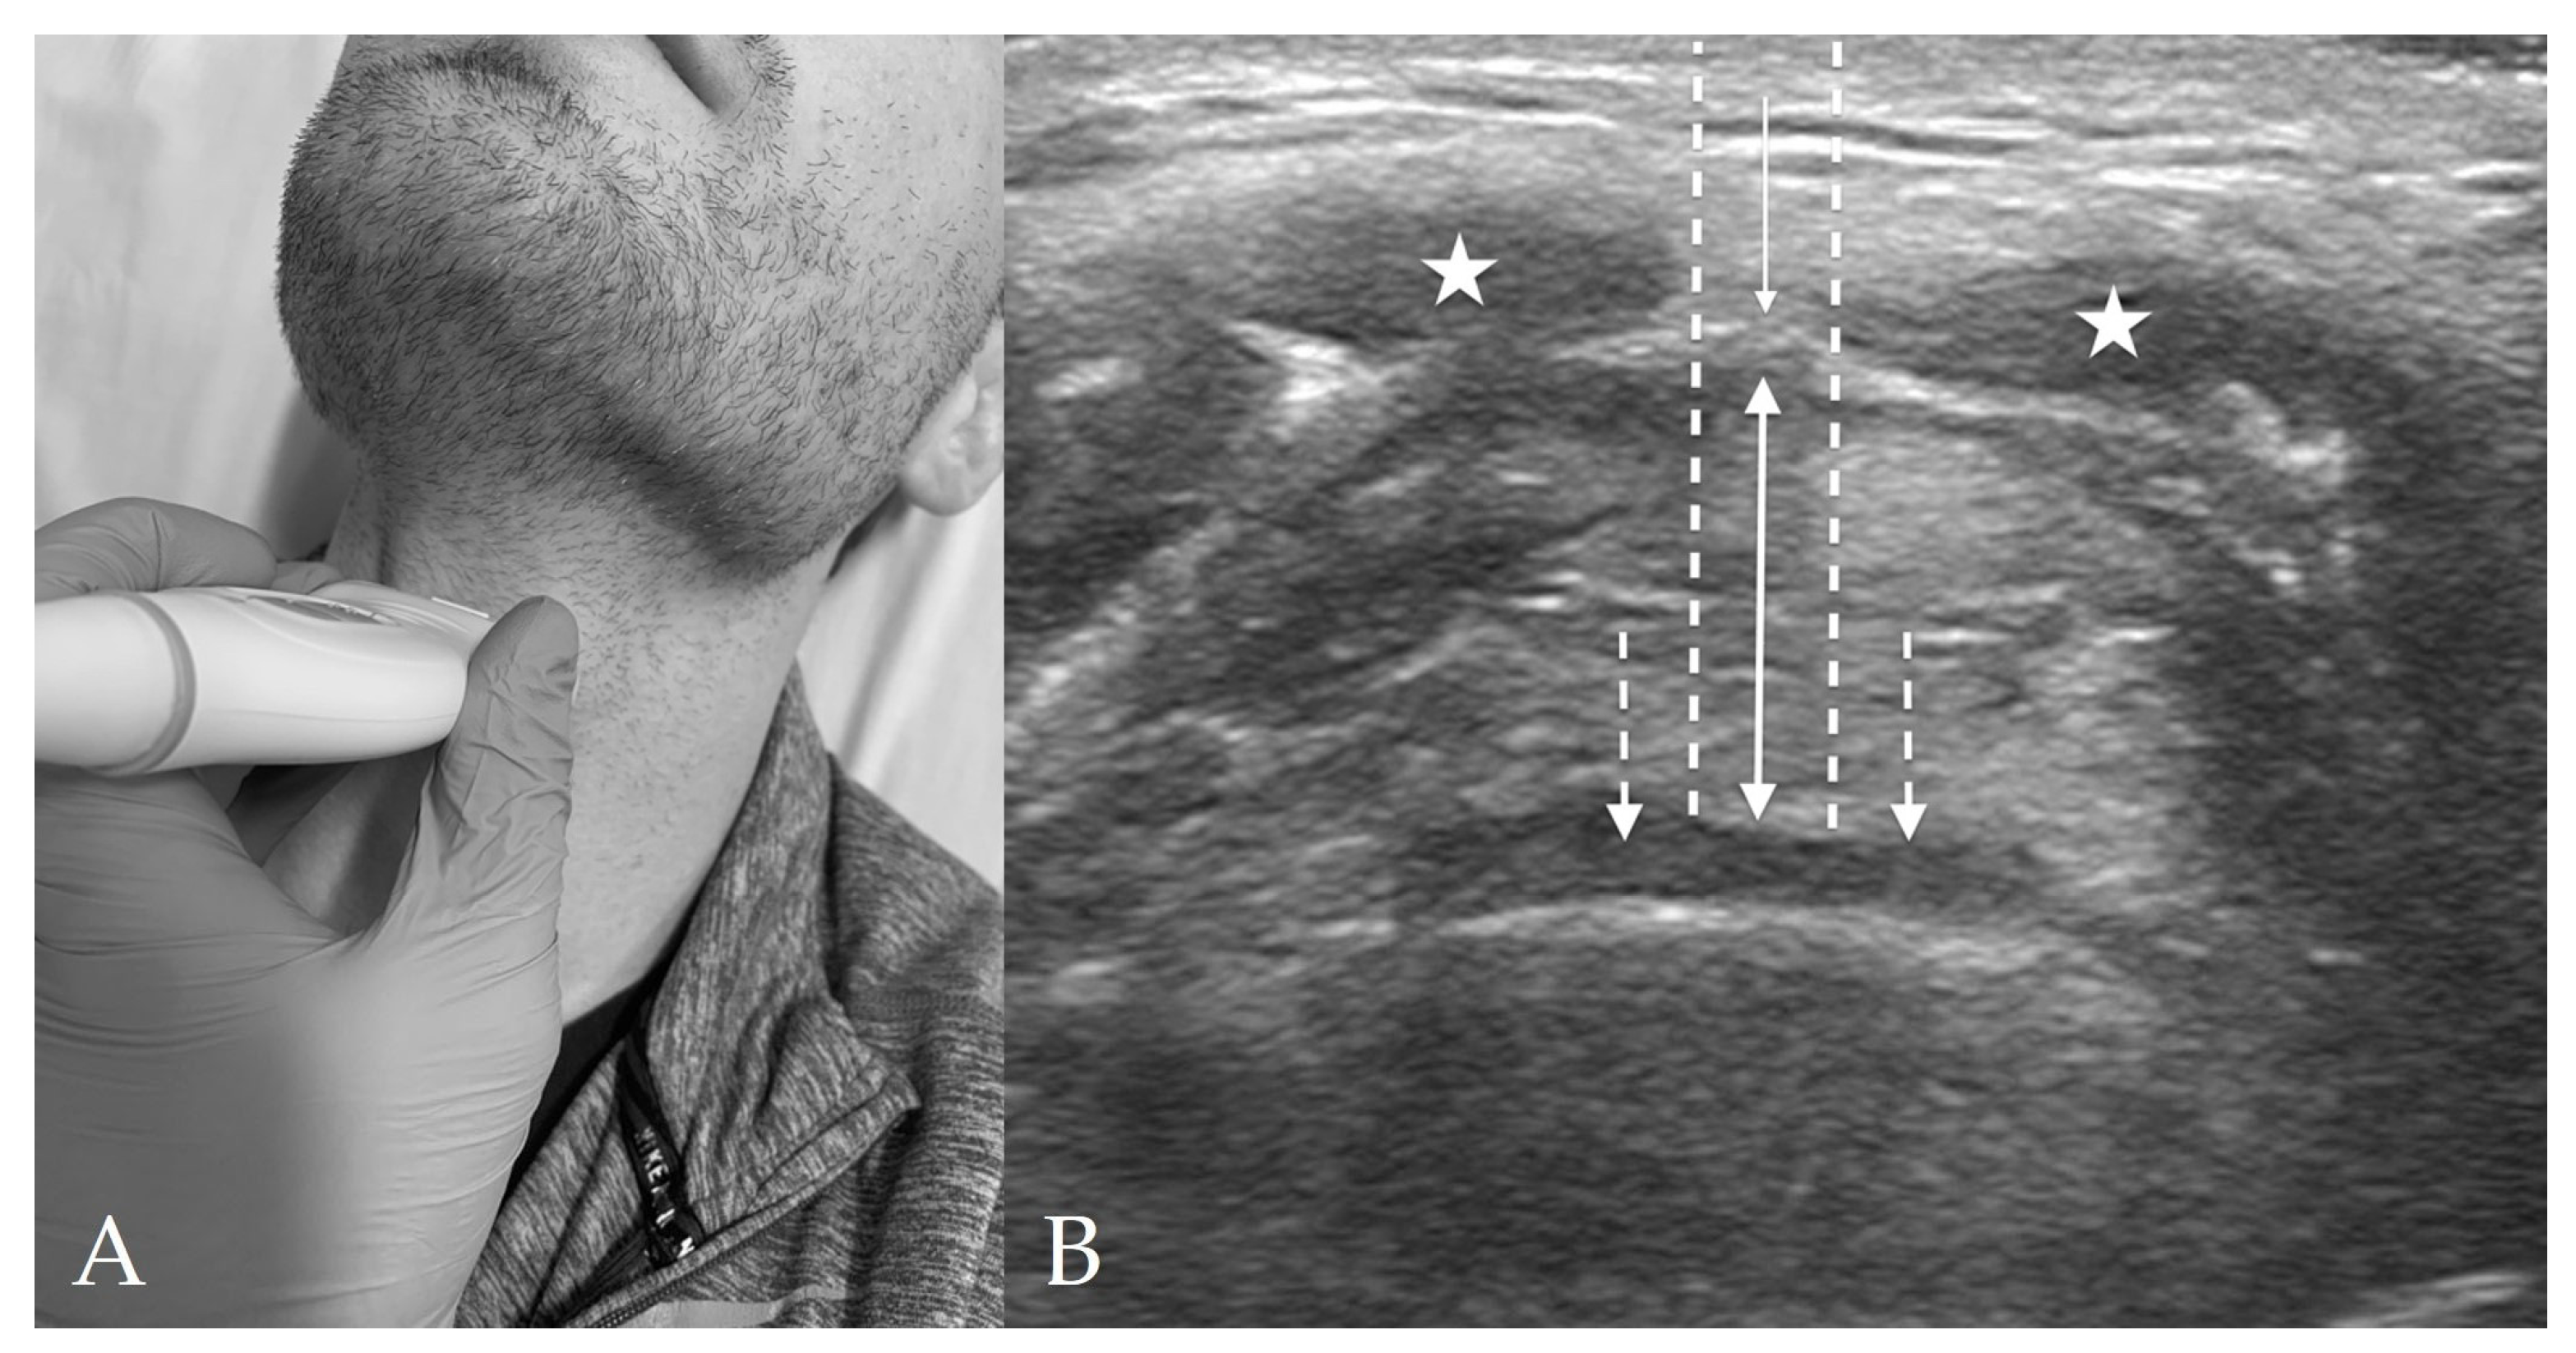

4.2. Thyrohyoid View

4.3. Thyroid View

4.4. Cricothyroid View

4.5. Suprasternal View